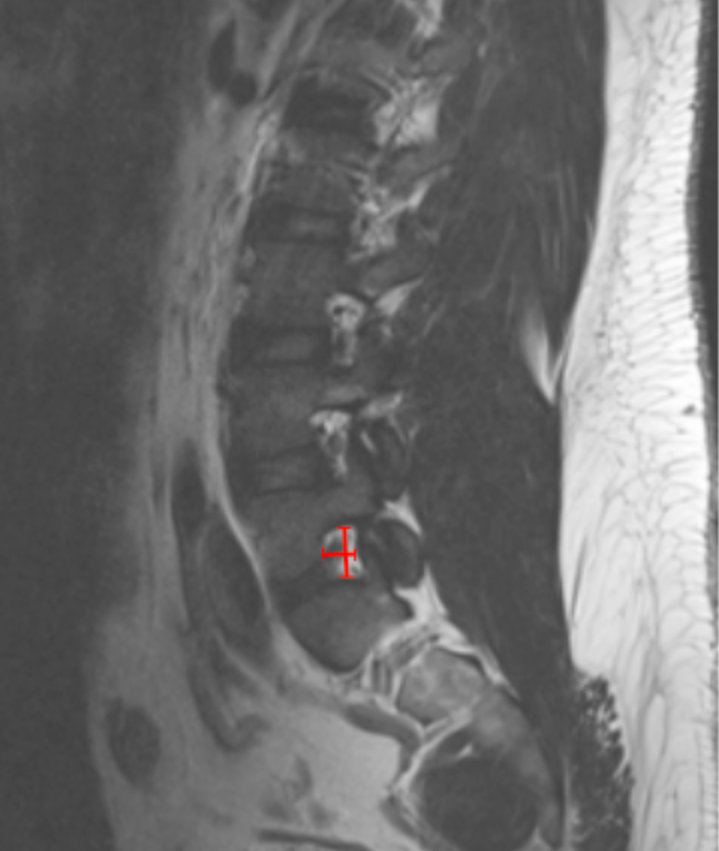

• On sagittal T2-weighted MRI, identify the disc level corresponding to the patient’s radicular symptoms.

• Select the parasagittal slice that best visualizes the neural foramen.

• Measure Foraminal Height:

• Identify the inferior cortex of the pedicle above and the superior cortex of the pedicle below.

• Measure the vertical distance (mm) between these two points.

• Measure Foraminal Width:

• On the same slice, identify the posterior vertebral body/disc margin (anterior boundary) and the anterior aspect of the superior articular facet (posterior boundary).

• Measure the anteroposterior distance (mm).